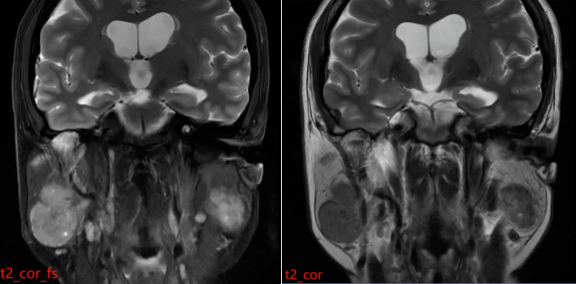

MR表现:双侧腮腺浅叶下极见结节状略混杂信号,T1以低信号为主、T2以 稍高信号为主,DWI呈稍高信号,ADC图呈稍低信号,边界清晰,增强扫描病变中等强化,强化较均匀,其内见点状无强化影。